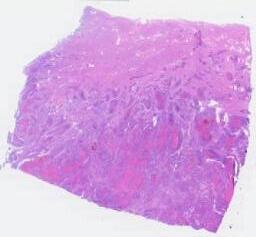

临床资料: 患者,女,57岁。现病史:1月前无明显诱因突然出现阴道出血,量少,色淡红,2周前阴道出血增多,色鲜红,如月经量,当地医院超声提示子宫内膜增厚,回声不均匀,宫腔镜诊刮病理:(宫内容物)高级别子宫内膜腺癌,考虑为去分化子宫内膜癌;MRI提示子宫后壁内膜增厚并不规则软组织肿块,侵犯深肌层。既往史:12年前卵巢成熟性畸胎瘤术后;脑梗;实验室检查:HPV(-),肿瘤标记物:CEA:7.78,CA125:22.9,CA199:10.5,鳞状上皮细胞癌抗原:1.19,AFP:3.84,HCG:0.93。